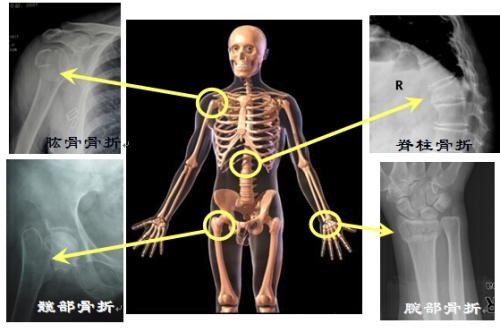

三、骨质疏松性骨折常见部位有哪些?

常见的骨折部位是脊柱、髋部、桡骨远端和肱骨近端,其他部位也可发生。